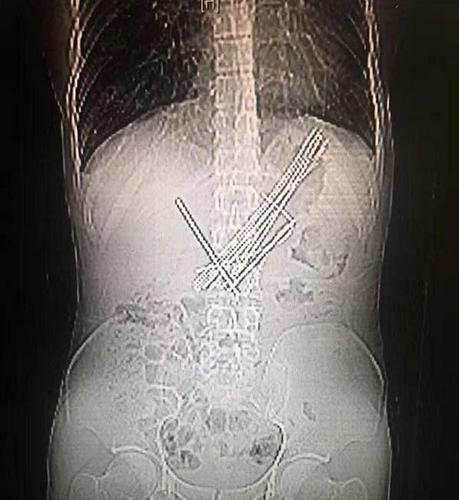

13枚钢针纵横交错、无序排列在嫌疑人的胃里,其中有两枚已经到达了小肠部位,危及生命。 复旦大学附属中山医院供图

为了不让其目的得逞,警方将其带至复旦大学附属中山医院,影像学检查结果显示,竟有十几枚钢针纵横交错、无序排列在嫌疑人的胃里,甚至有两枚已经到达了小肠部位。

该院内镜中心医生迅速制定出缜密的手术方案,将嫌疑人胃里已经折弯的钢针一一取出,最终发现共有13枚,整个手术非常成功,共花费了2个小时。